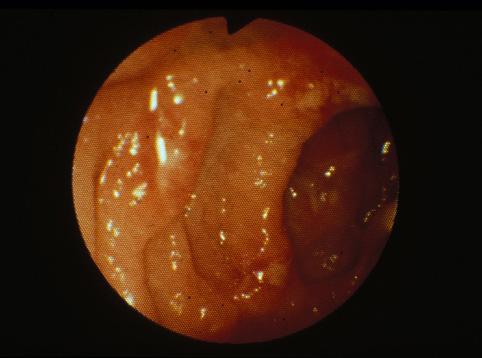

疾病(病理主体)的分类炎症性・溃疡性疾患/阿米巴痢疾

部位(按器官分)大肠/盲肠

检查方法内窥镜